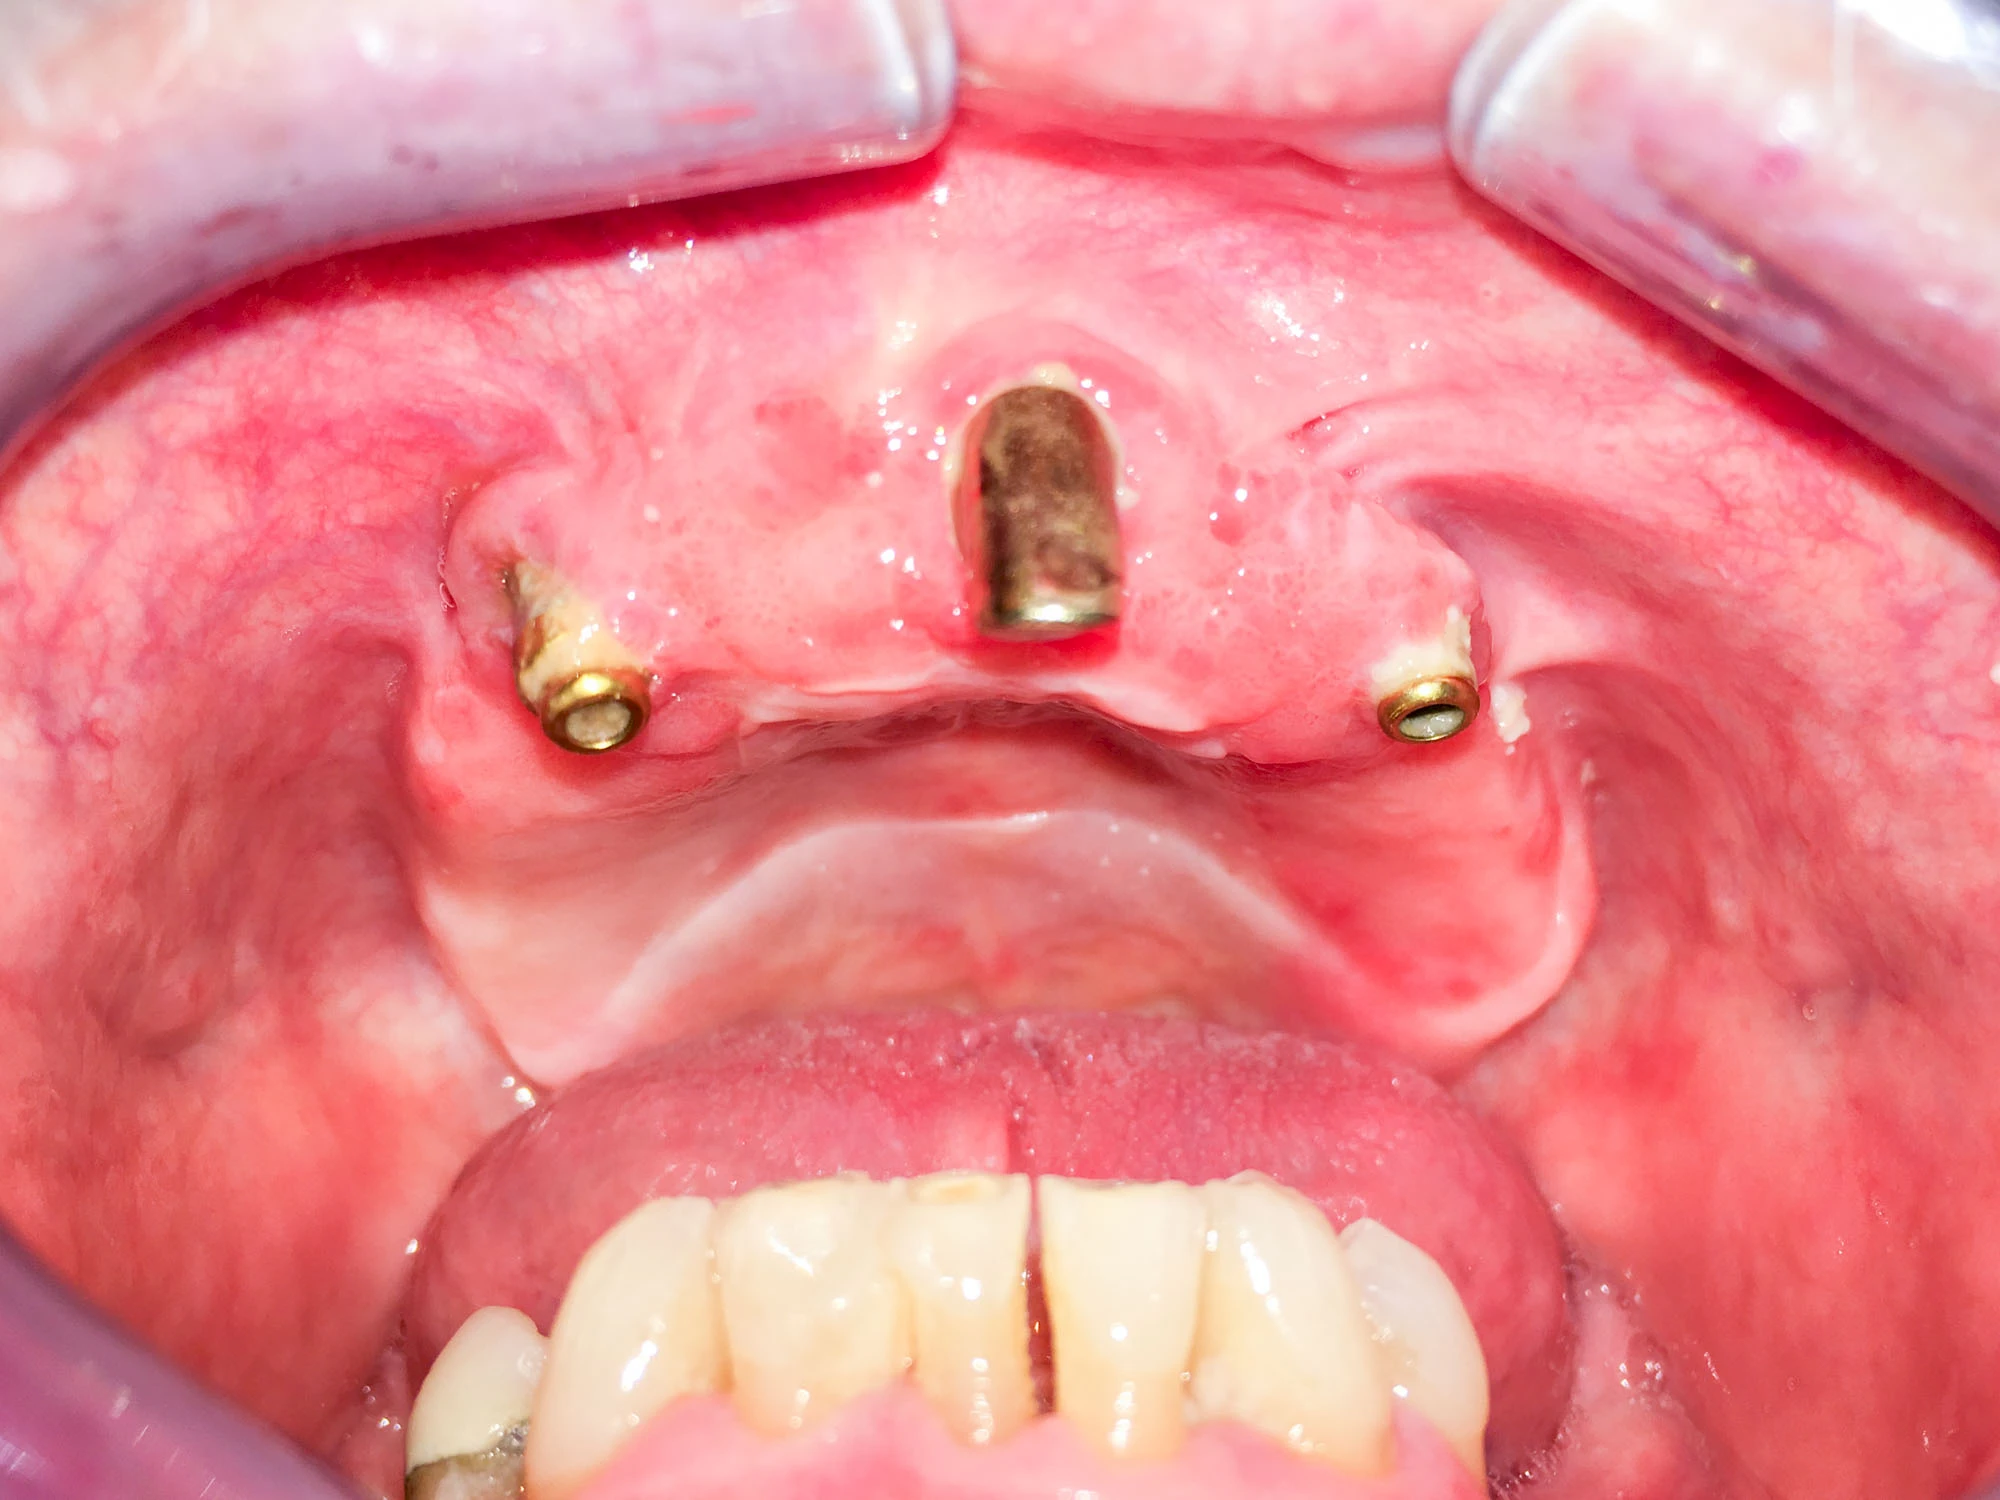

Bei Implantaten – also operativ eingebrachten künstlichen Zahnwurzeln – kann der Körper die Bakterien auch nicht so gut abwehren. Hier spricht man im Fall einer Entzündung von einer Peri-Implantitis, also einer Entzündung um das Implantat herum.